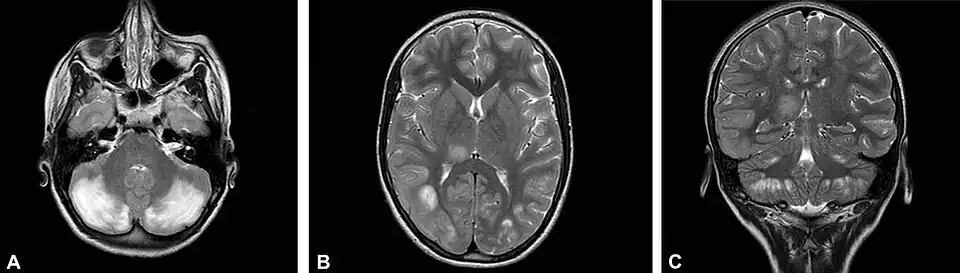

Наиболее ярко ЦФН проявляется при мутациях гена FOLR1, отвечающего за доставку фолатов в центральную нервную систему[4][5]. Ребёнок с мутацией рождается здоровым. Заболевание дебютирует чуть позже - в раннем детском возрасте - такими симптомами, как задержка психомоторного развития, атаксия, тремор, хорея, миоклонические приступы. На МРТ-снимках может наблюдаться гипомиелинизация. При немедленном назначении фолиновой кислоты можно добиться значительного улучшения состояния.

До и после возобновления терапии лейковорином при недостаточности ДГПР